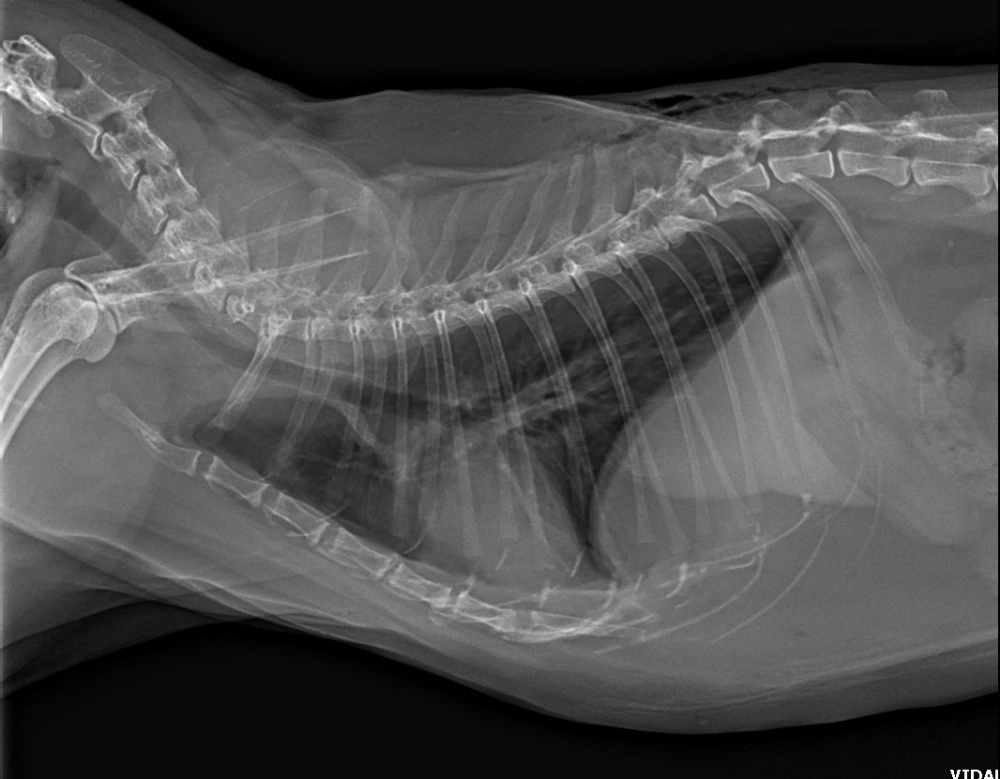

Raio x cães

A importância do raio x cães na medicina veterinária

Nesse sentido, o raio x cães desempenha um papel essencial na medicina veterinária, permitindo visualizar estruturas internas e identificar possíveis problemas de saúde.

O raio x é um exame de imagem que utiliza radiação para obter imagens de ossos, órgãos e tecidos moles.

No caso dos cães, o raio x pode ser utilizado para diagnosticar fraturas, identificar corpos estranhos, avaliar órgãos internos e detectar doenças respiratórias, entre outras condições.